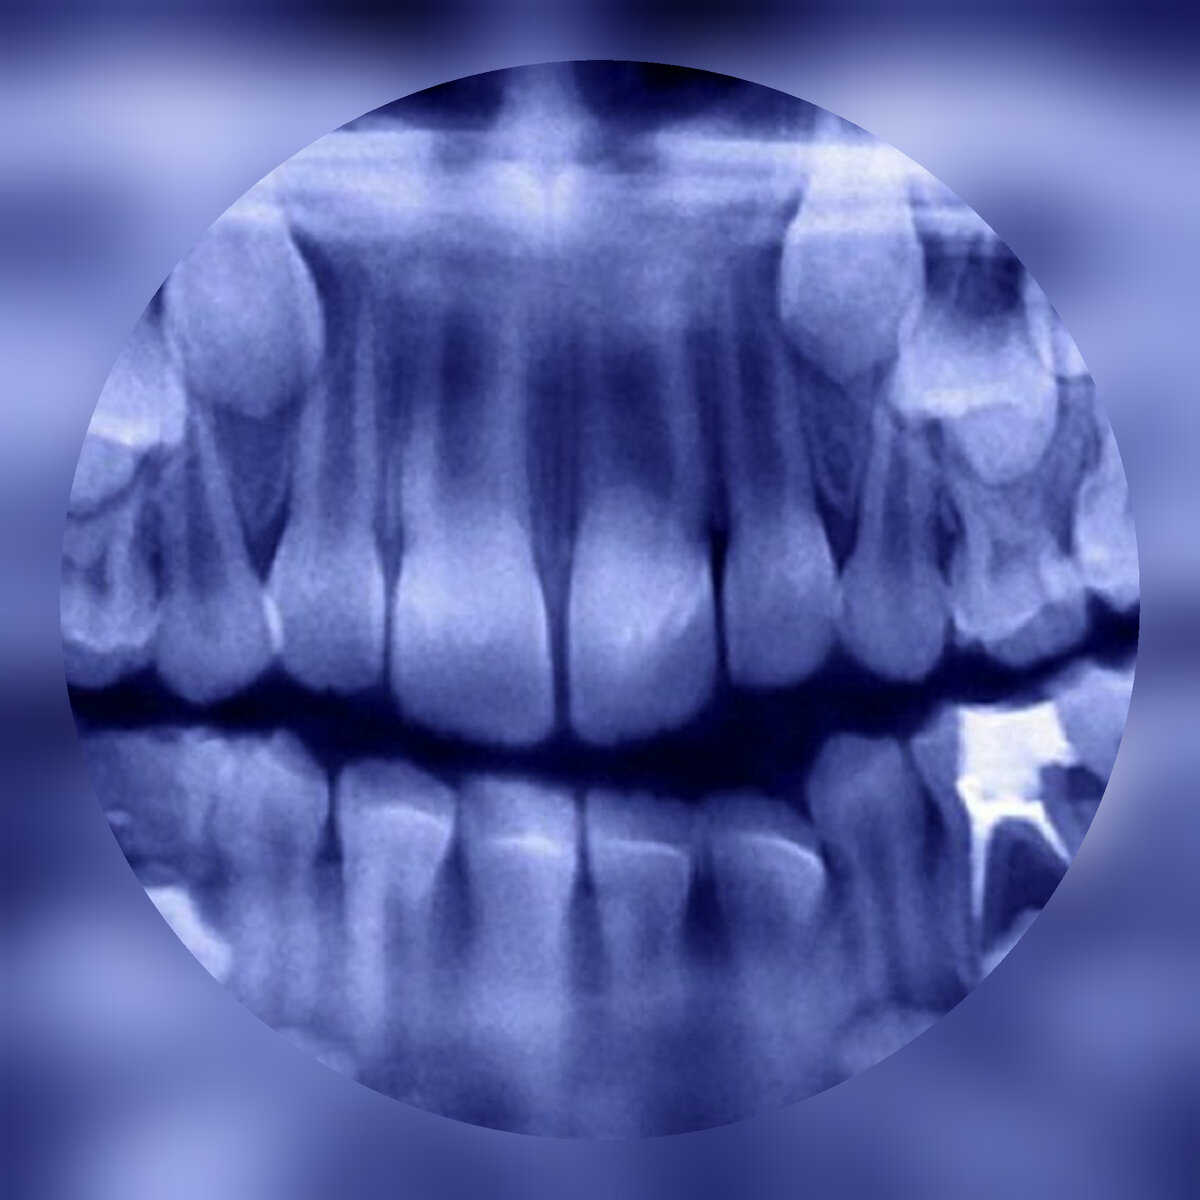

Снимок зубов

Равиндранат (так звали мальчика) с трёх лет жаловался на боль в челюсти. Врачам он не разрешал смотреть и принимать какие-либо медицинские вмешательства. Когда мальчик оказался в кабинете стоматолога, то сначала врачи решили что это кариес, сделав рентген, они на снимке заметили не что другое, много крошечных зубов. Маленькие зубки были врощенны в нижнюю часть челюсти рта, но их не было видно снаружи. У мальчишки была опухшая щека и сильная боль.